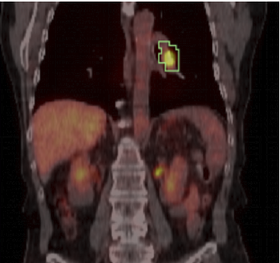

This module computes Standardized Uptake Value (SUV) based on patient body weight, using a PET image and one or more manually drawn VOIs. SUV-bw for VOIs of different color (id) will be assessed separately.

This module can be used to quantify tumor response to treatment. Typically, an initial PET/CT study is done prior to treatment, and a followup study is registered to it. ROIs can be specified on the initial study and used to compute SUVmax-bw and SUVmean-bw on both studies.